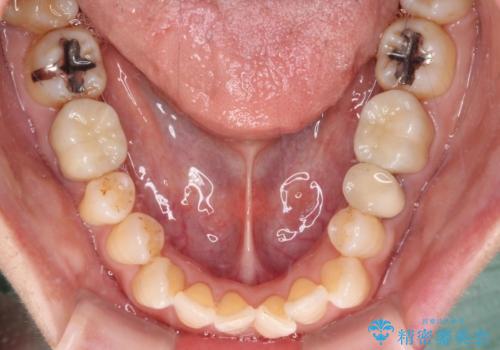

銀歯を白くしたい セラミックによる審美歯科治療

知覚過敏の症状はなくなり、希望通りの白い歯になったと、患者様は大変満足されました。